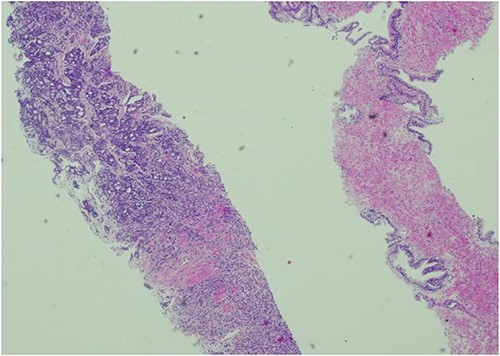

The patient was then referred to the urology department by the Head & Neck MDT. As part of his workup, a digital rectal examination (DRE), PSA test, prostate biopsy, and bone scan were recommended, and gonadotropin-releasing hormone (GnRH) antagonists were started. The DRE revealed a mildly enlarged, firm, smooth prostate with no nodularity. The PSA level was 1271 ng/dl, which decreased to 639 g/L within 1 week of the commencement of treatment. Transrectal ultrasound revealed a prostate volume of 54 cc and a local anaesthetic transperineal template biopsy of the prostate revealed prostatic adenocarcinoma with 4 out of 12 cores from the right gland with a Gleason Score of 4 + 5 and 1 out of 12 cores from the left gland with a Gleason Score of 5 + 5. The mean overall Gleason score was 5. Additional features included a cribriform pattern and perineural invasion (Fig. 3). Bone scans revealed multiple areas of increased tracer uptake, including the skull vault and skull base, cervical spine, thoracic spine, lumbar spine, and pelvis, with multiple bony metastases (Fig. 4). Therefore, the staging of the disease was T1c N0 M1b, high-risk, or Cambridge Prognostic Group 5.

Histology of prostatic tissue showing adenocarcinoma. Gleason score 5 + 4 = 9, Gleason group 5. 5/24 cores were positive for adenocarcinoma.